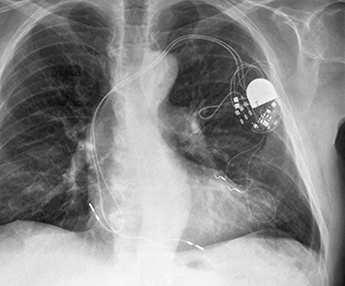

Transvenous pacemakers are the older, tried-and-true version. We make an incision under the left collarbone, and one, two or three wires, or leads, are navigated through a vein into separate locations in the heart. At the other end they are connected to a small generator that has a battery and circuitry. The generator sits just under the skin beneath the incision. It’s designed to be replaced every seven to 10 years, depending on the heart’s pacing needs.